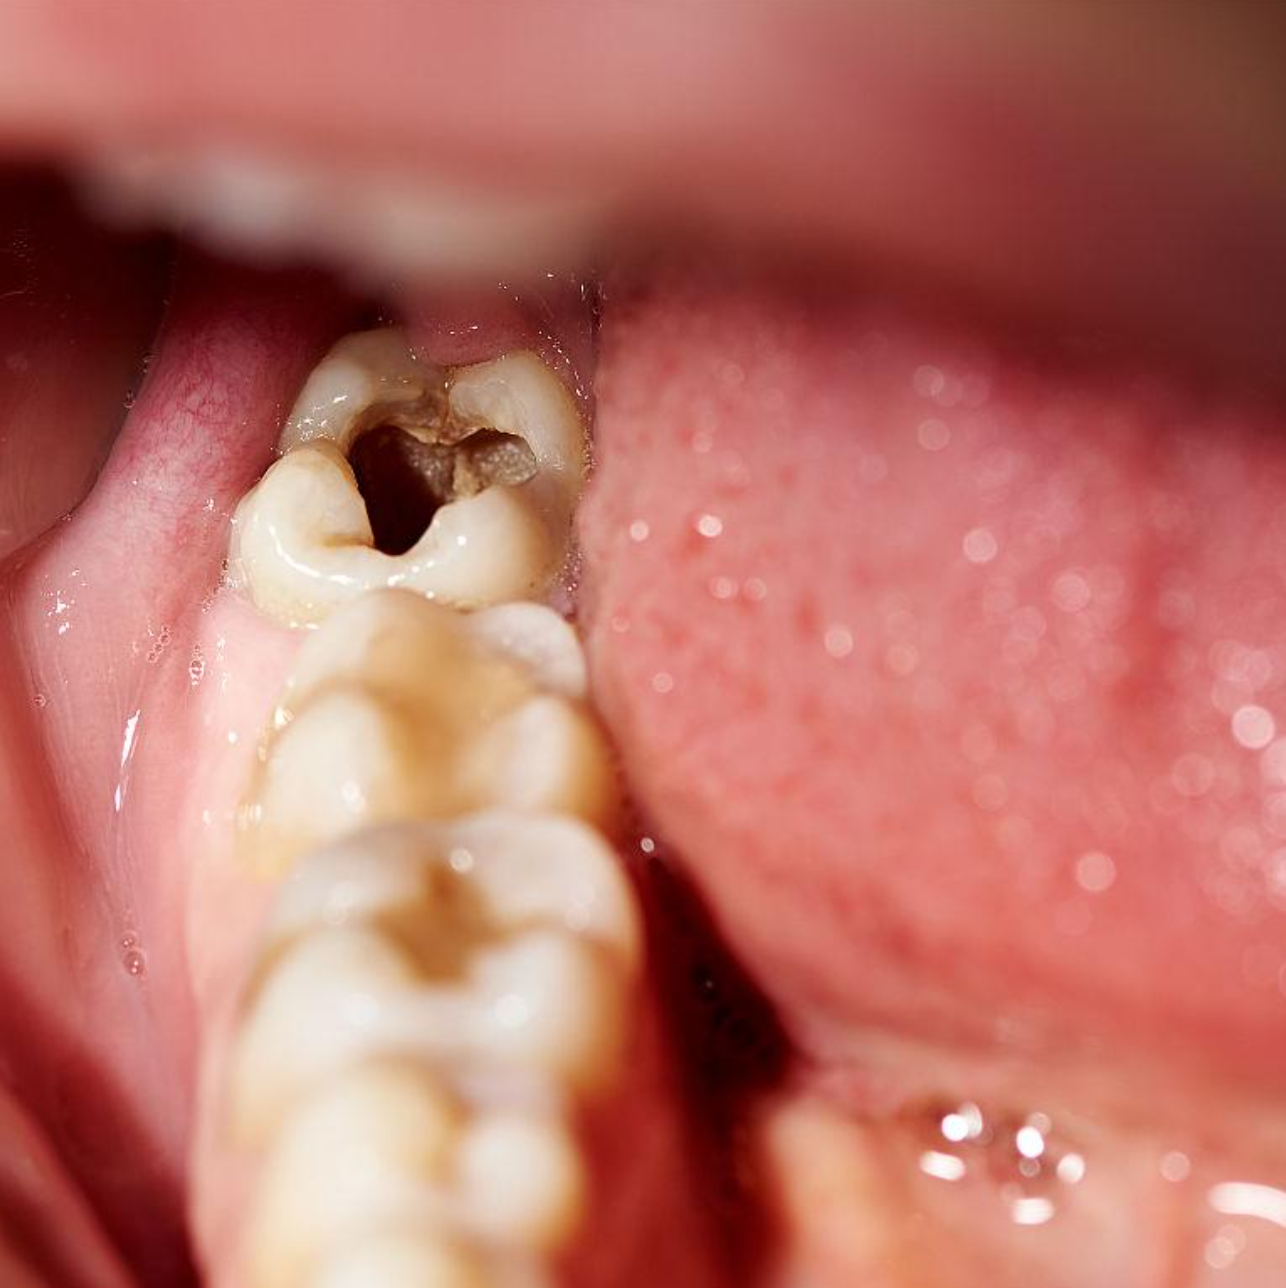

颊舌向阻生智齿拔除1例